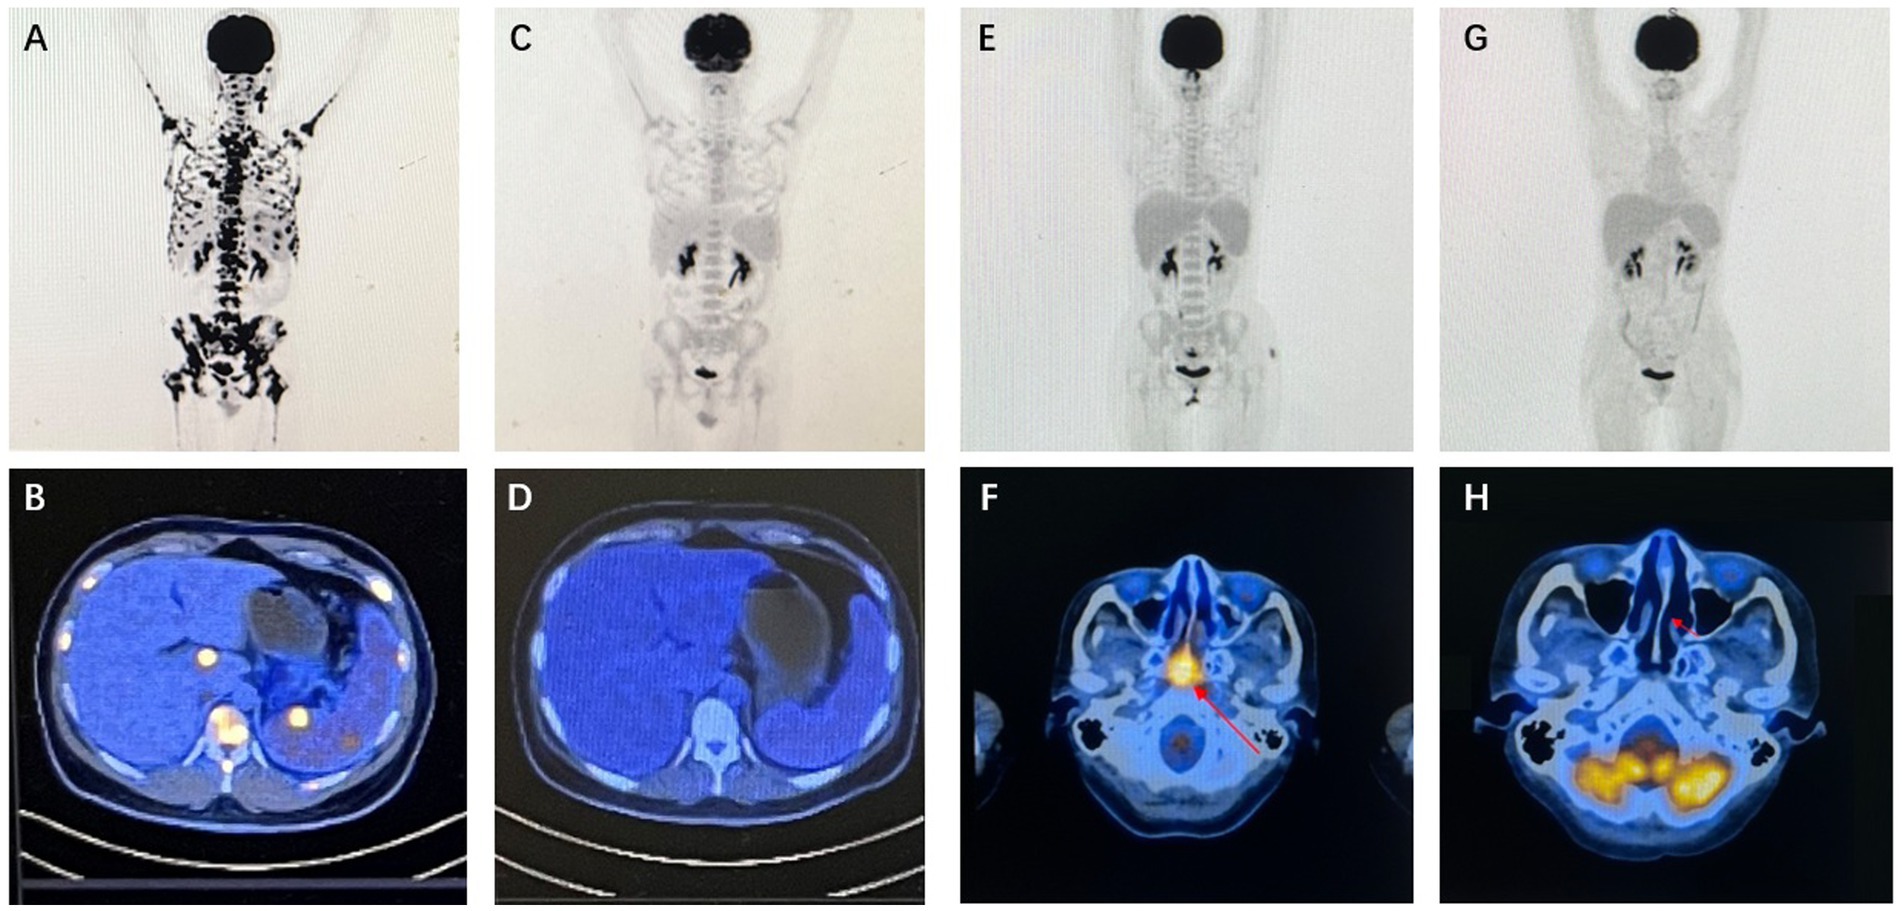

A series of medical imaging scans. Image A shows a full-body skeletal scan with numerous dark spots. Images C, E, and G display progressive clearing of these spots. Images B and D show cross-sectional scans of the abdomen with decreasing bright areas. Images F and H show axial brain scans with highlighted areas. Each image pair (A-B, C-D, E-F, G-H) illustrates changes in medical observations over time.

Figure 3. Imaging findings of representative patients. Case 20 PET/CT results: baseline PET/CT demonstrated systemic lymph node involvement, splenomegaly with focally increased metabolic activity, and concurrent intramedullary lesion infiltration (A,B). Following two cycles of P3-GemOx therapy, follow-up PET/CT confirmed complete resolution of all FDG-avid lesions, achieving complete response (CR) (C,D). Case 22 PET/CT results (study obtained after initial chemoradiotherapy): baseline PET/CT revealed soft tissue thickening with intensely increased metabolism in the posterosuperior wall and bilateral walls of the nasopharynx, suggestive of neoplastic lesions (E,F). After two cycles of P3-GemOx therapy, follow-up PET/CT documented complete resolution of all FDG-avid lesions, confirming complete response (CR) (G,H).

A median of three cycles (range, 1–4) of the P3-GemOx regimen were administered, with every patient showing an objective response. Among these, seven of the nine patients achieved complete response (CR), while two attained partial response (PR). Normalization of EBV DNA was observed after one or two cycles of therapy. Seven patients successfully undergoing hematopoietic stem cell transplantation (HSCT), and other three patients rejected for personal reasons. Notably, one patient (case 9) experienced disease progression due to poor compliance and lack of standard treatment but still achieved CR after just one cycle of the P3-GemOx regimen. Another patient (case 5), initially received two cycles of COEPL regimen, did not achieve PR but later reached PR following three cycles of P3-GemOx regimen. We present the imaging findings of two representative patients: One patient (case 20) initially presented with systemic lymph node involvement and intramedullary lesion infiltration (Figures 3A,B). Refractory to prior P-GemOx combined with Chidamide therapy, the patient achieved remarkable regression of all lesions after receiving the P3-GemOx regimen at our institution, attaining complete response (CR) following two treatment cycles (Figures 3C,D). Another patient (case 22) initially presented with tumor involvement confined to the nasopharynx (Figures 3E,F), but exhibited suboptimal response to initial P-GemOx plus radiotherapy. After receiving two cycles of P3-GemOx therapy at our institution, the patient achieved complete response (CR) (Figures 3G,H). Both patients met the criteria for and subsequently underwent allogeneic hematopoietic stem cell transplantation (allo-HSCT) following completion of P3-GemOx therapy. To date, they have maintained favorable clinical status post-transplantation. In this group, both the 1-year progression-free survival (PFS) and overall survival (OS) rates were reported at 100%. Patients receiving this regimen exhibited a tendency for improved PFS and OS (Figure 4).